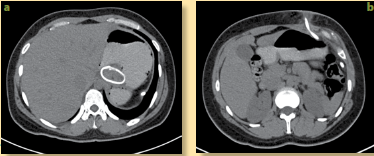

Se llevó a cabo una tomografía computada (TC) simple con contraste oral de control, en la que se observa la banda gástrica en posición correcta, sin evidencia de colecciones ni líquido libre; sin embargo, sí se observa el tubo conector exteriorizado, y con un proceso inflamatorio agregado (figura 1a y 1b).

Figura 1 Estudio de tomografía computada (TC) antes del retiro de banda gástrica. a) TC de abdomen con contraste oral, corte axial a nivel del estómago, en donde se observa una imagen metálica redonda de la unión esofagástrica en relación a banda gástrica. b) Corte axial de TC en donde se observa una imagen lineal metálica desde el estómago hasta el tejido celular subcutáneo en relación al tubo conector con cambios en la densidad de la grasa alrededor por severo proceso infamatorio.